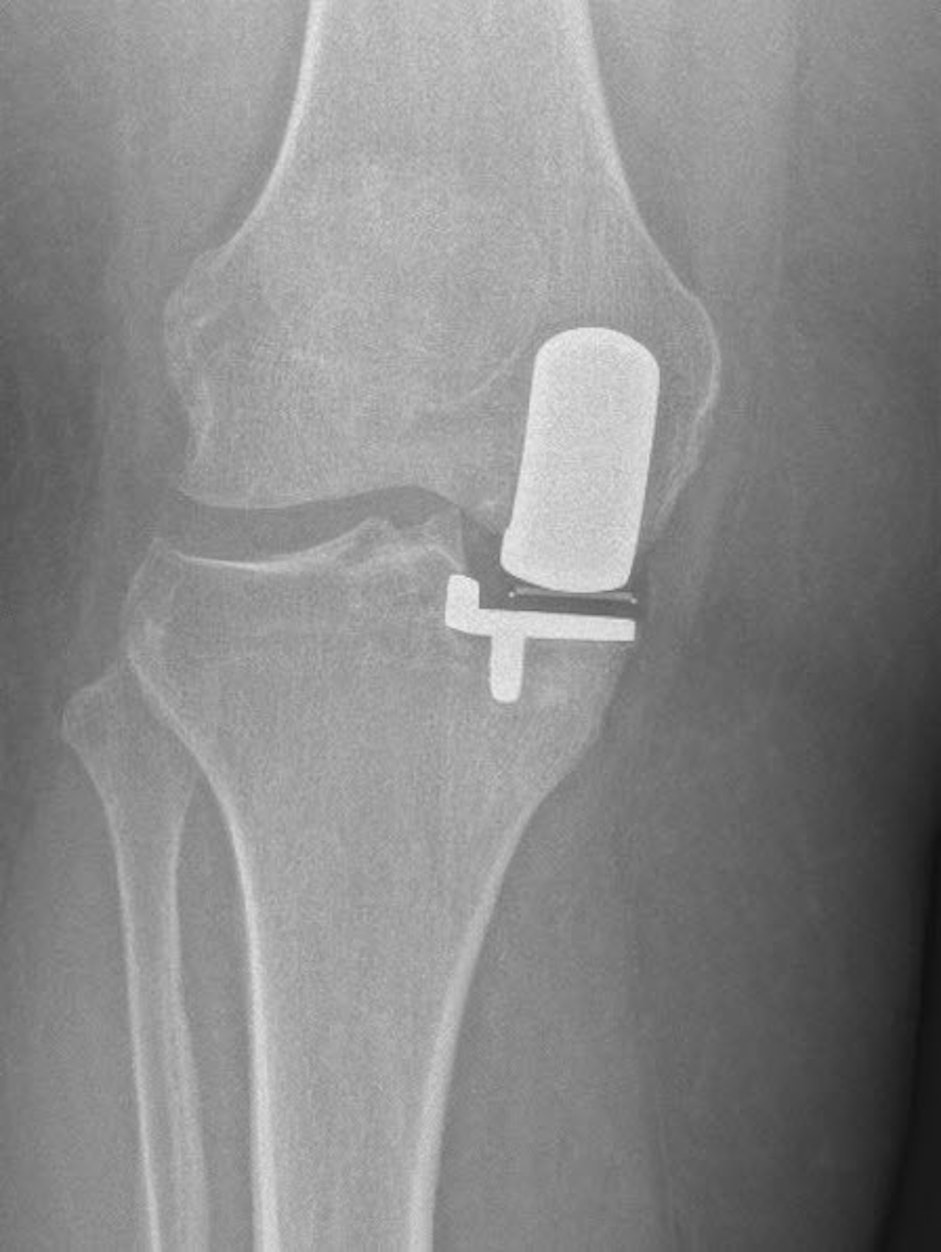

Bij een unicompartimentele knieprothese (UKP) - halve knieprothese in de volksmond - vervangen we enkel het versleten gewrichtscompartiment.

De prothese bestaat uit 3 componenten: een bolvormige component die op het dijbeen wordt geplaatst en een vlakke component die op het dragend deel van het scheenbeen wordt geplaatst. Daartussen zit een mobiele component die de functie van de meniscus overneemt.

De componenten die gefixeerd worden op het dijbeen en op het scheenbeen bestaan uit een Chroom Kobalt Molybdenum legering. Daartussen zit een mobiel polyethyleen component dat gemaakt is uit ultra high moleculair weight polyethylene (UHMWPE).

Er zijn twee methoden om de componenten te fixeren: met botcement of cementloos. In de meeste gevallen gebruiken we de cementloze techniek. Bij de cementloze techniek groeit het bot van de patiënt in een speciale hydroxie-apatiet laag van de prothesecomponenten in. De keuze tussen de twee technieken hangt onder andere af van de botkwaliteit van de patiënt. Bij heel kleine patiënten of bij zwakke botkwaliteit fixeren we de prothese doorgaans mét cement.